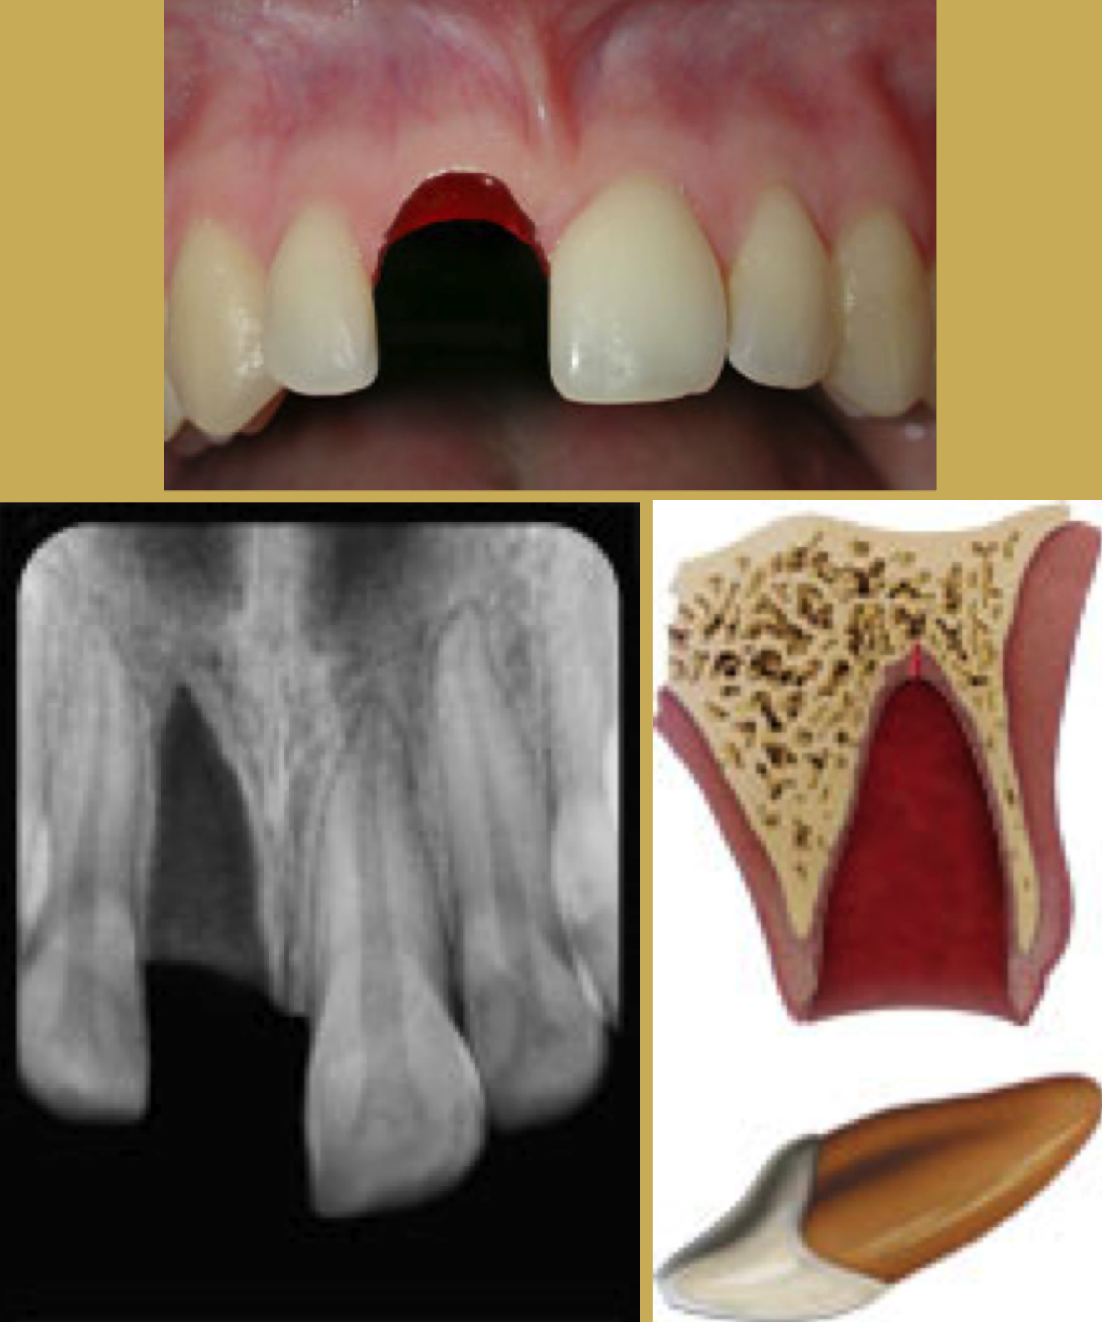

Most blows to the mandible do not result in fractures, yet significant force can be transmitted to the temporomandibular disc and supporting structures that may result in permanent injury (Figure 1 and Figure 2). In both mild and severe trauma, the condyle can be forced posteriorly to the extent that the retrodiscal tissues are compressed. Inflammation and edema can result forcing the mandibular condyle forward and down in acute malocclusion. Occasionally this trauma will cause intracapsular bleeding, which could lead to ankylosis of the joint.

Fig 1. TMJ Landmarks

Figure 1

Fig 2. Dimensional Image of TMJ

Figure 2